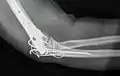

تصوير شعاعي جانبي لمفصل الكوع الأيمن.

تصوير شعاعي لمفصل الكوع الأيمن: قطع عظم.

جراحة إعادة تثبيت عظام الساعد.